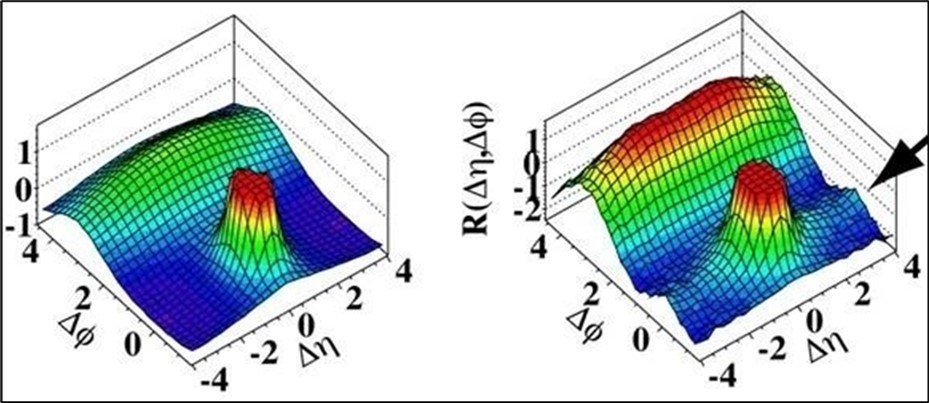

It is a non–invasive method. It can be used to monitor the chemical changes of tissues. We can simultaneously evaluate several metabolites. Two examples of where MRS is very helpful in the brain: The invasion of the tumor (Glioblastoma multiform (GBM) into the surrounding tissues, which is not clear in normal T2 images, but can be determined by MRS. By MRS, it is possible to distinguish two types of lesions that look similar to each other in normal MRI images (such as tumor recurrence and tumor necrosis after radiotherapy). MRS imaging has found wide applications in the field of cancer diagnosis. Among the fields of clinical application of MRS, we can mention the diagnosis (between normal and cancerous tissue, different types of cancer and neoplastic from non–neoplastic), designing the best treatment regimens for each patient, and monitoring the patient after treatment. MRS in tumors: In brain tumors, spectroscopy can determine the degree of malignancy. As malignancy increases, NAA and creatine decrease and choline, lactate and fat increase. Fat is seen in the necrotic parts of the tumor. Lactate concentration increases in rapidly growing tumors due to anaerobic glycolysis. Diagnosing tumor recurrence from the effects of radiotherapy: Increased choline is a marker for tumor recurrence. Changes due to radiotherapy usually decrease NAA, creatine and choline. If necrosis has occurred as a result of radiotherapy, fat and lactate can also be seen in the spectrum. Molecular imaging using spectroscopy Cerebral ischemia and infarction: When the brain suffers from ischemia, anaerobic respiration of glucose is used and lactate increases. Choline increases and NAA and creatine decrease. If it happens after ischemia, the fat signal is also seen. trauma: It is a useful method to assess the degree of nerve damage and predict the results. The clinical consequences are opposite to the NAA/Cr ratio, and the observation of lactate and fat indicates the seriousness of the condition. infectious diseases: decrease naa Inside the abscess, lactate, alanine, cytosolic acid and acetate increase. Alzheimer: In the advanced stages of Alzheimer's, NAA decreases and myo–inositol increases. MS: The increase of choline and lactate has shown that the increase of choline can be due to the increase of phospholipid as a result of breaking the myelin of the cell and the increase of lactate is due to the increase of the anaerobic respiration of the cell due to the increase of the cell metabolism. In addition, there is evidence of increased lipids, and most importantly, decreased NAA, which is caused by nerve damage. And recently, it has been found that glutamate and myoinositol levels increase in acute MS lesions. Parkinson: In most studies in Parkinson's disease, no changes in metabolites have been observed, only when Parkinson's has caused brain atrophy, a decrease in NAA in the basal ganglia has been observed (Figure 3, Figure 4, Figure 5, Figure 6).

Figure 6.Simulation of CERN Large Hadron Collider (LHC) radiation source for magnetic resonance biospectroscopy in metabolic (left) and molecular (right) imaging and diagnosis of cancer.